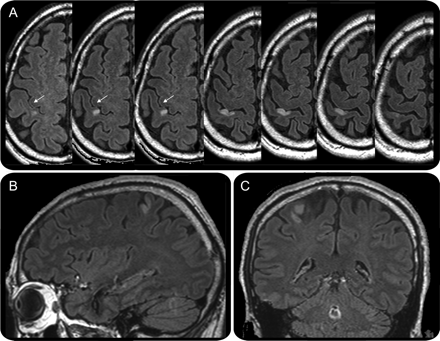

图2

MRI: (A)轴向,(B)矢状,(C)冠状图像fluid-attenuated反演复苏后5天开始显示急性梗死的前部分正确的中央后回

病变位于内侧,优,后方中央前把手区(箭头所指)。